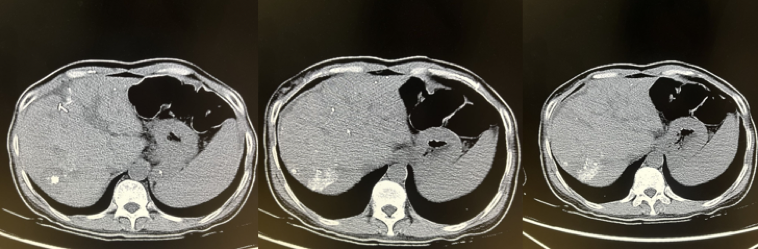

2020年7月21日术后MR检查:下腔静脉肝后端及双肾水平处,左肾静脉、右肝门区扩张静脉、肝内部分侧枝血管内栓子形成(图2)。

图2.2020年7月21日术后MR

2020年8月21日复查MR示(图3),肝癌术后表现,下腔静脉内栓子,右肾静脉可疑异常信号(栓子?)。

图3.2020年8月21日复查MR